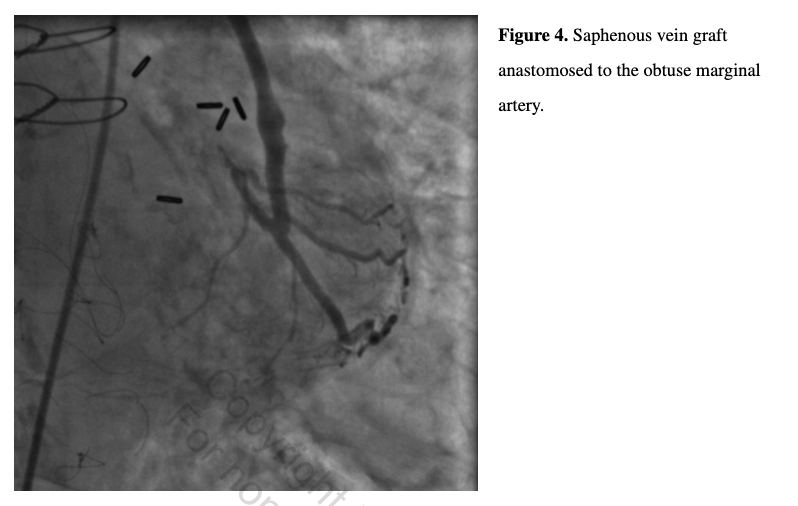

She subsequently underwent further testing, including computed tomography (CTA) of her aortic root and bilateral iliofemoral arteries (aortic valve annulus, 369 mm2; 69 mm perimeter; 20.6 mm diameter; bilateral common iliac arteries with 5 mm mean luminal diameters), three-dimensional transesophageal echocardiography, and cardiac catheterization. Invasive coronary angiography revealed unchanged chronically occluded LAD, LCX, and RCA, and patent SVGs to the distal LAD and OM (Figures 3 and 4). Notably, the RIMA and LIMA grafts were somewhat atretic, but patent and with normal antegrade flow to the anterior and lateral LV myocardium, respectively (Figures 5 and 6), despite competitive filling from patent SVGs.